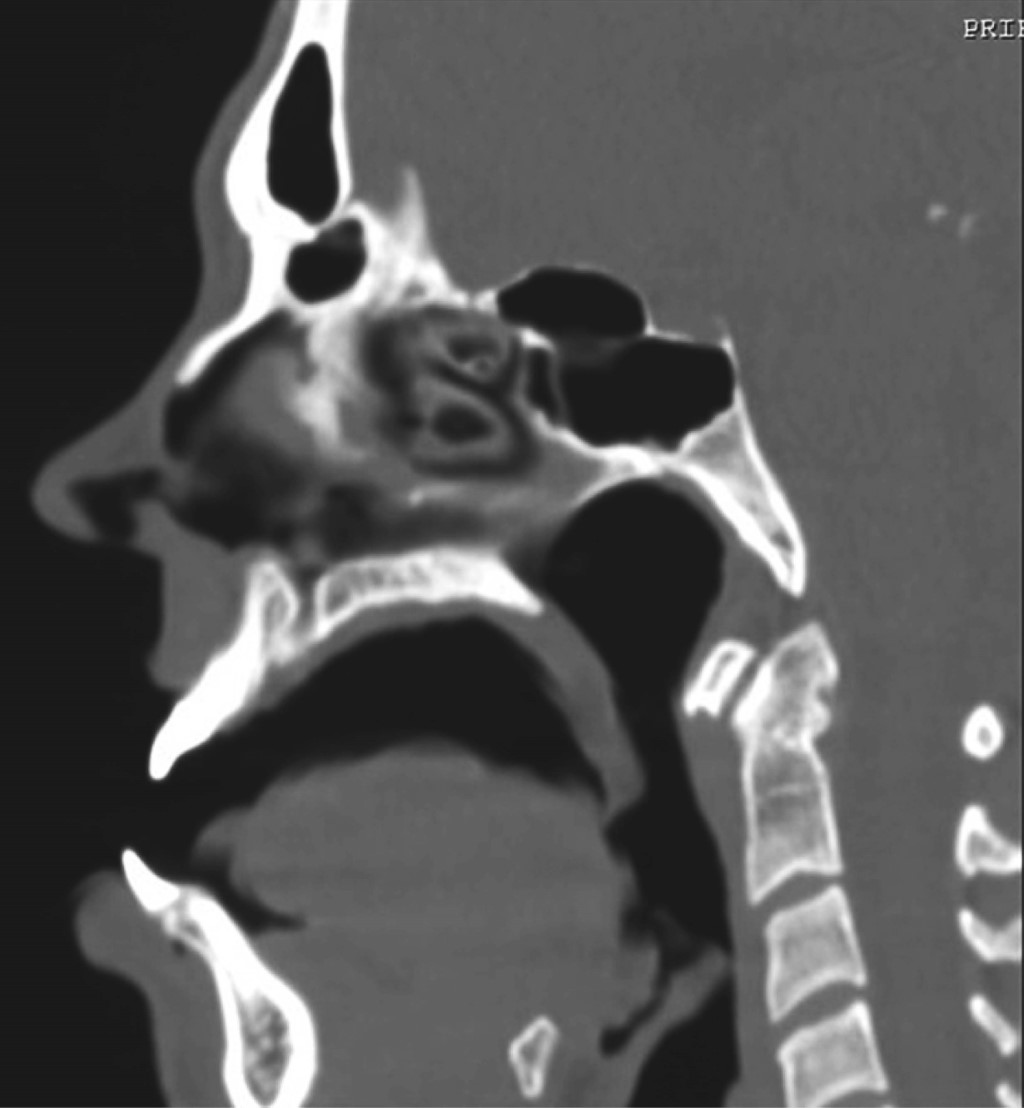

A computed tomography did not show bone erosion, palatal bone pathology, or any other pathologies in the surrounding areas that might explain the origin of the palatal lesion (Figure 3).

Figure 3